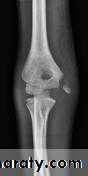

Lateral condyle fracture of humerus:

Fractures involving the lateral condyle of the humerus & account about 17% of all distal humerus fractures in the pediatric population,typically occurs in patients aged 5-10 years old,most commonly are Salter-Harris IV fracture patterns of the lateral condylemechanism of injury :

Imaging

Radiographs

recommended views

AP, lateral, and oblique views of elbow

internal oblique view most accurately shows maximum displacement and fracture pattern .